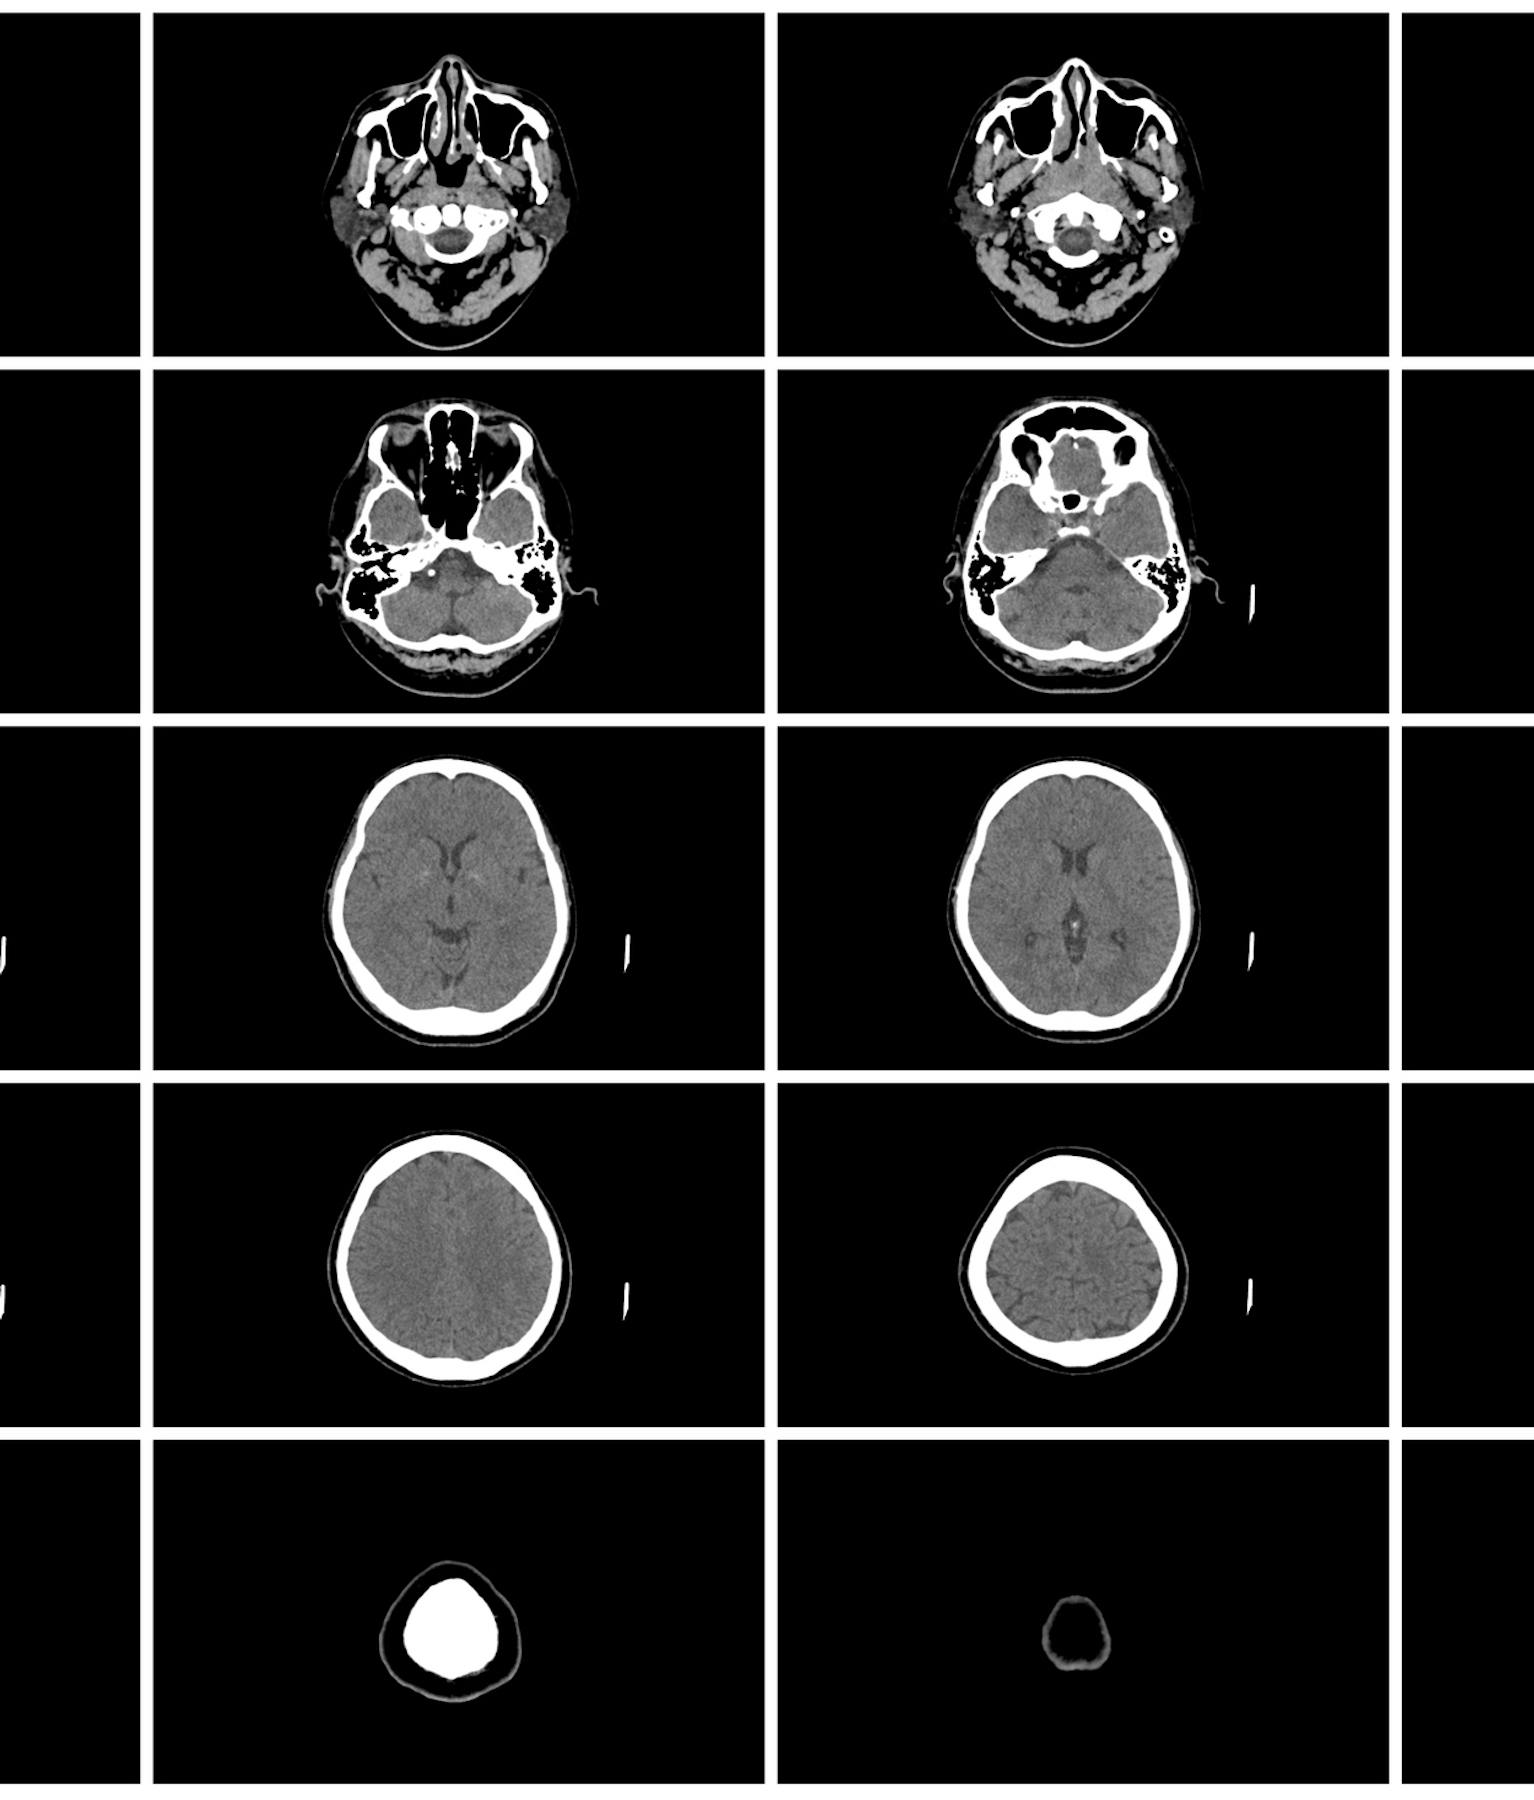

La chirurgie spinale (chirurgie de la colonne vertébrale pour les affections de la nuque et du dos) est pratiquée dans notre hôpital, ainsi que le traitement (via les urgences) de lésions intracrâniennes sévères, telles que les hémorragies cérébrales et la traumatologie.